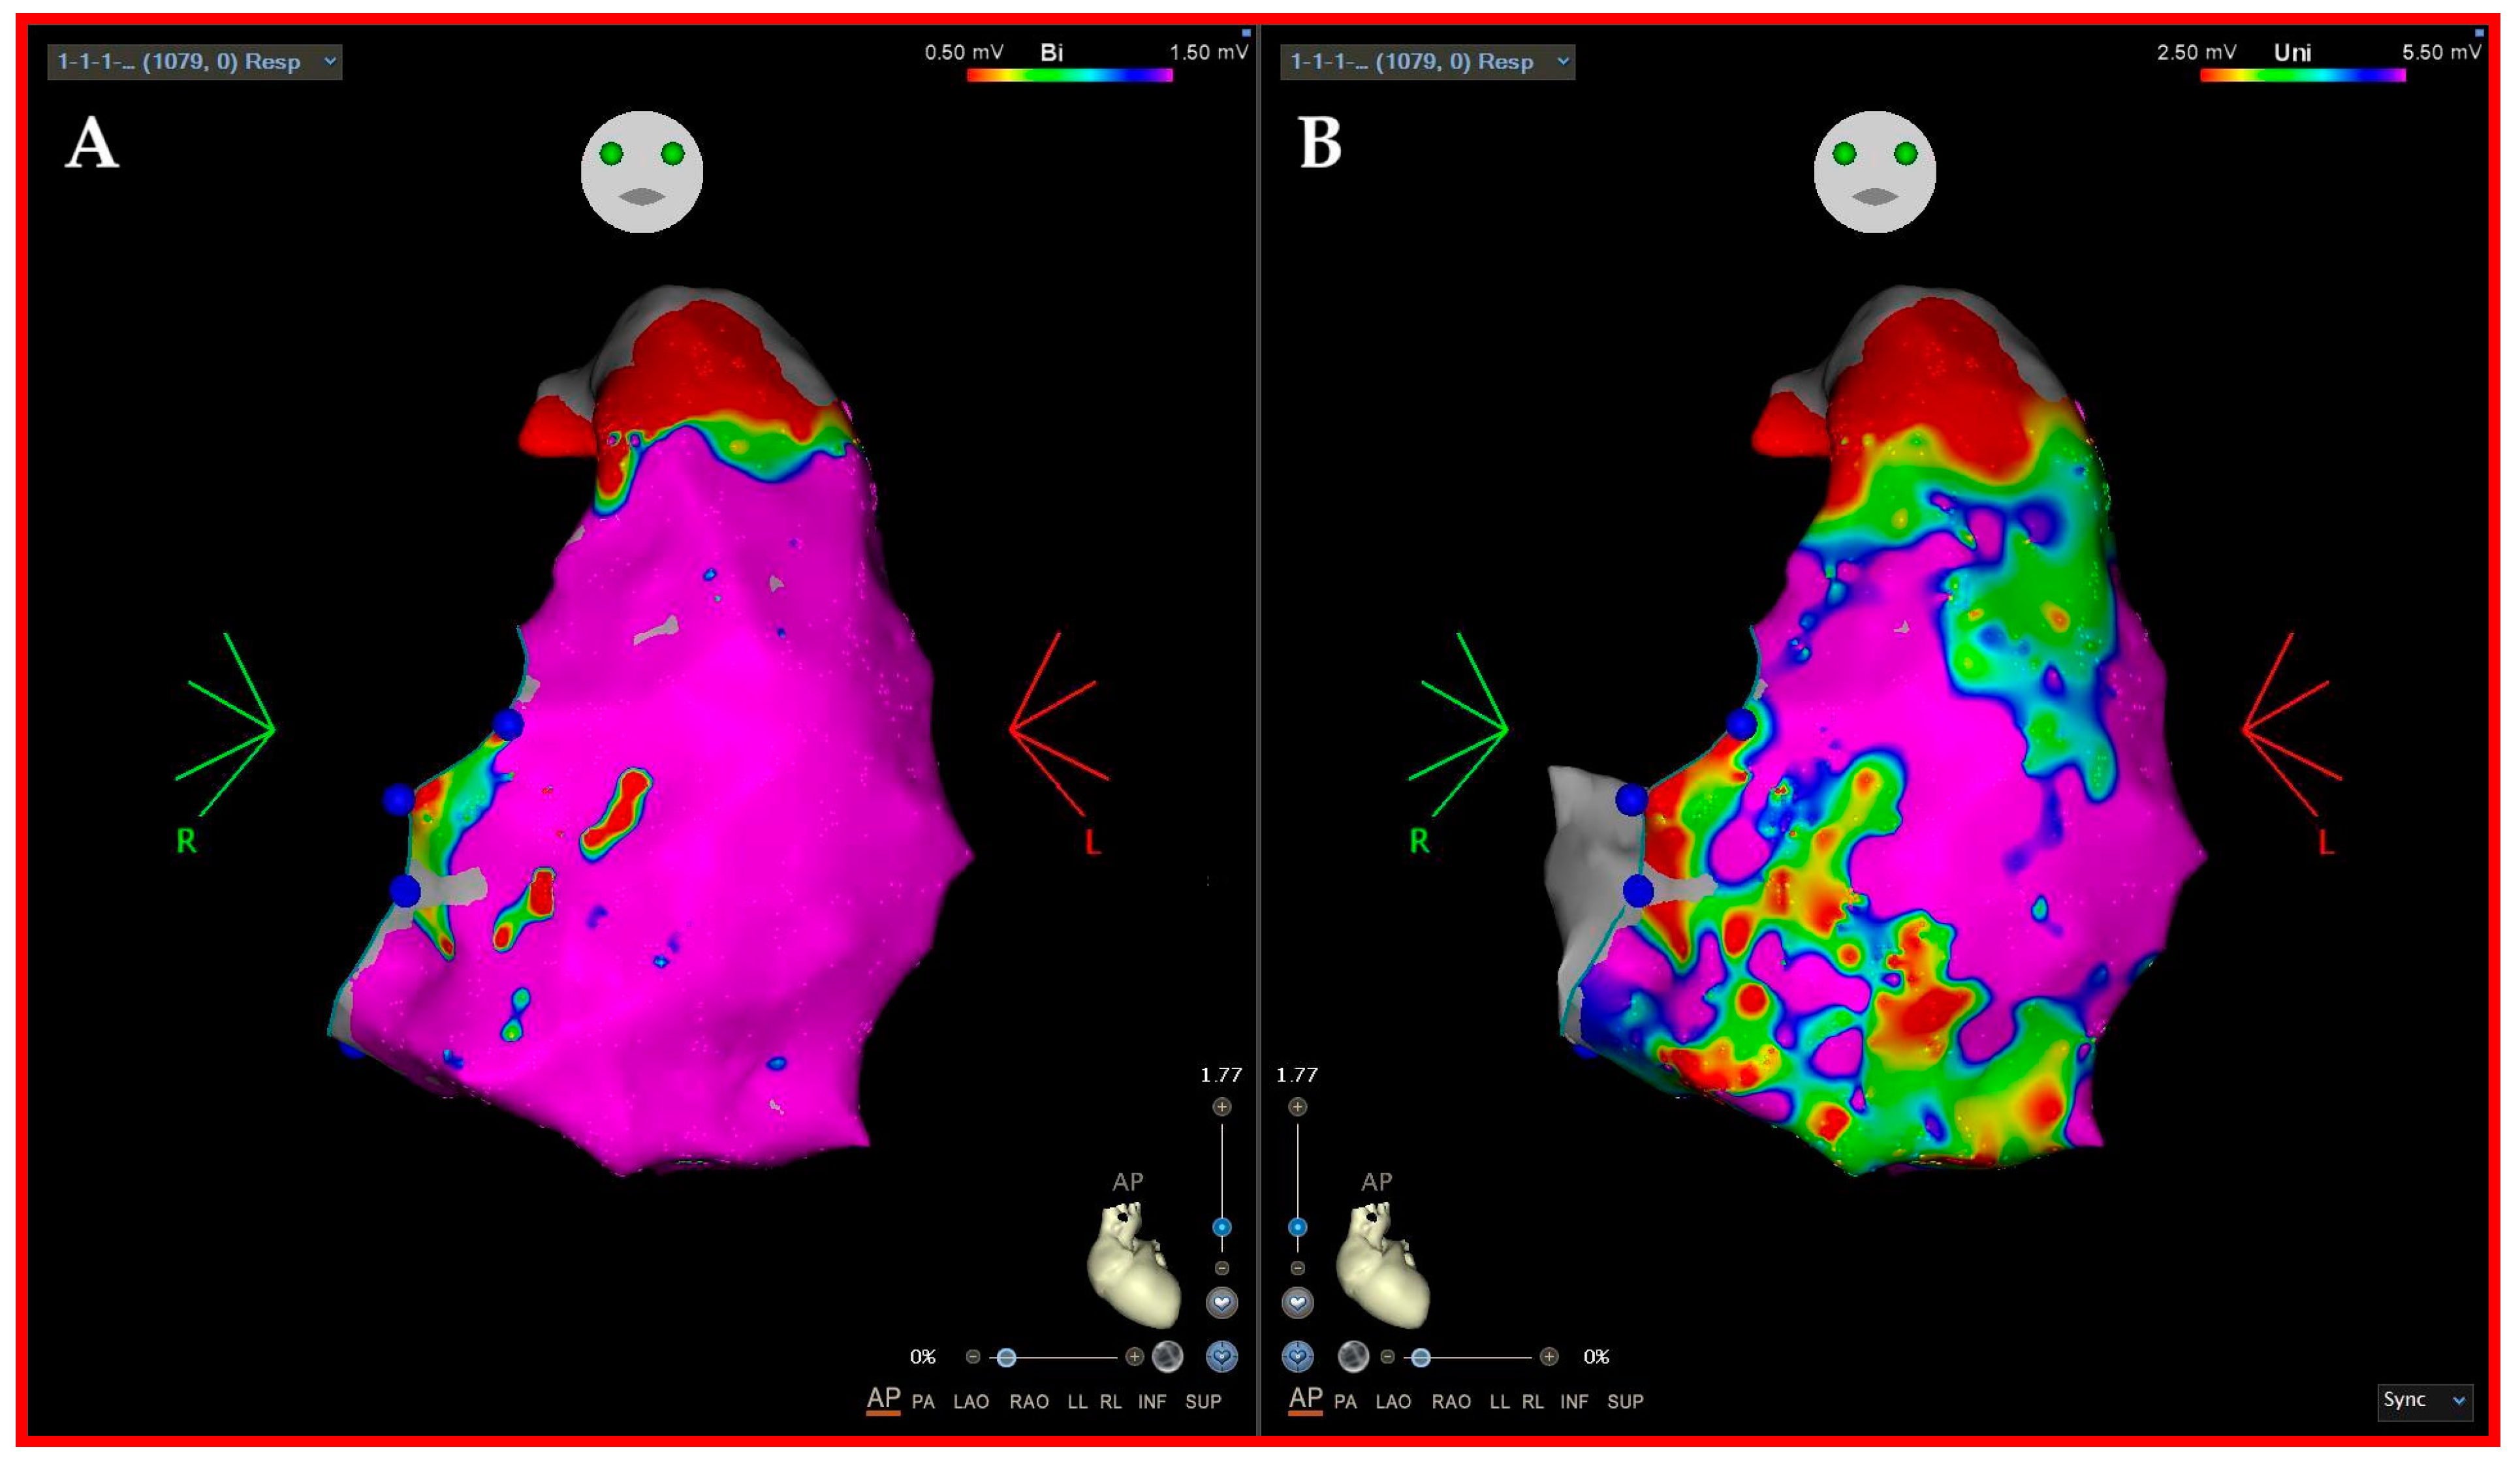

3.2. Three-Dimensional (3D)-Mapping Systems

4. Our Experience and Workflow

- A detailed substrate high-density mapping in sinus or paced rhythm (voltage, LAVA, LPs, DeEP mapping) performed by a multipolar-mapping catheter;

- Complete substrate modification (elimination of all LAVA/LP/DeEP);

- Re-mapping the ablated areas with a multipolar high-density mapping catheter;